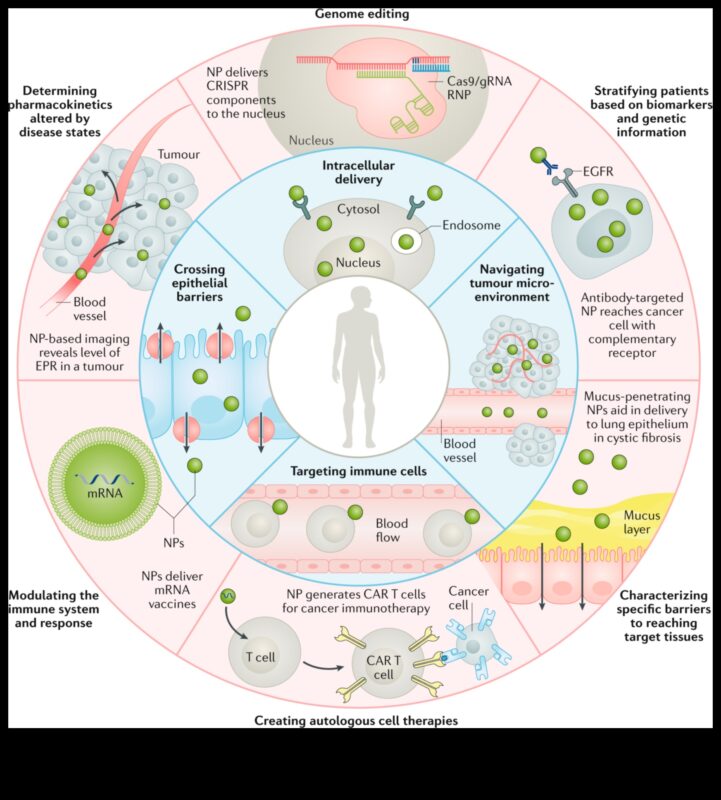

- Διεύρυνση τελευταίων ιατρικής και θεραπειών για ασθένειες.

Διεύρυνση τελευταίων ιατρικής και θεραπειών για ασθένειες.